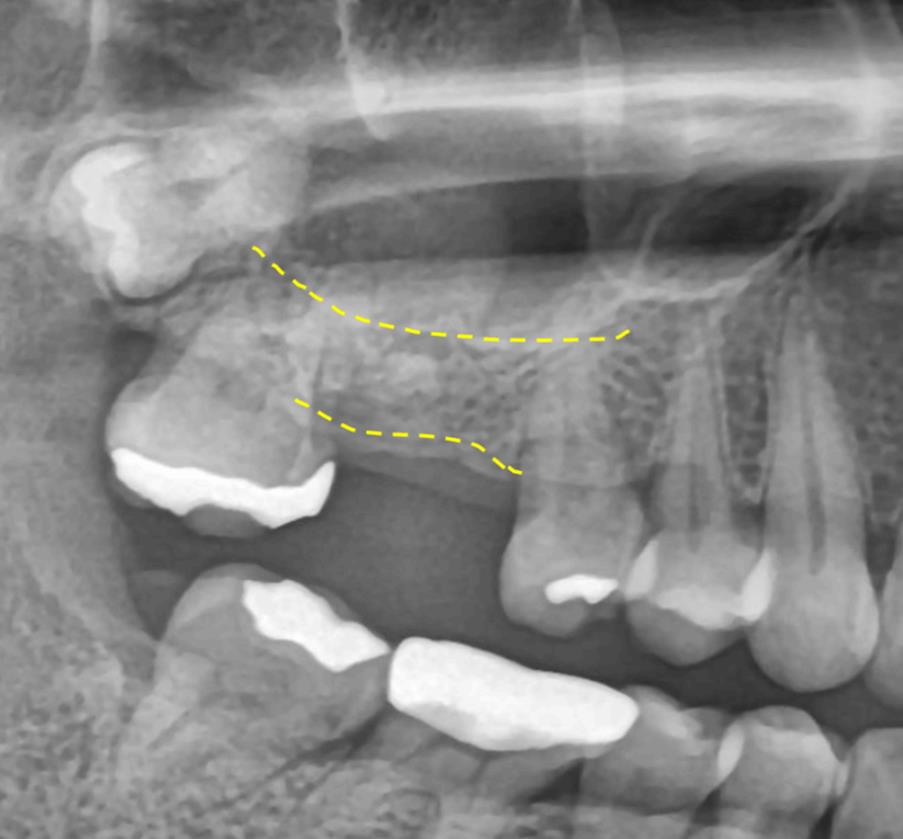

수술 전 파노라마 – 상악동과 인접한 위치 확인

수술 전 CT – 뼈 높이가 부족해 상악동 거상술 필요 소견